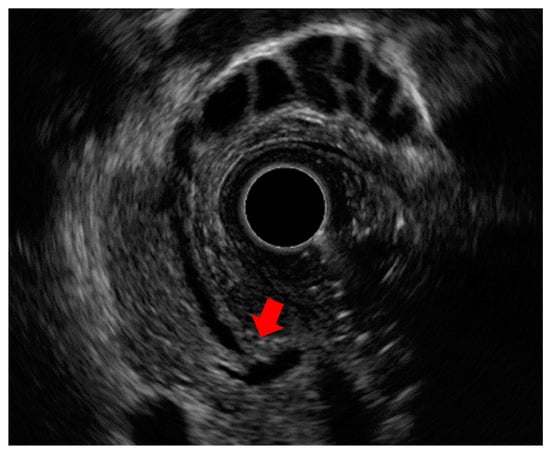

7.1. Diagnosis of Choledocholithiasis

- Catanzaro, A.; Pfau, P.; Isenberg, G.A.; Wong, R.C.; Sivak, M.V., Jr.; Chak, A. Clinical utility of intraductal US for evaluation of choledocholithiasis. Gastrointest. Endosc. 2003, 57, 648–652. [Google Scholar] [CrossRef] [PubMed]